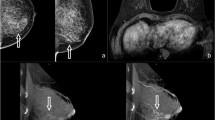

Diagnostic test accuracy results by each imaging modality are summarised in Table 3. Figures 2 and 3 aid in visual interpretation of the imaging modality accuracy and reader performance. Case reports demonstrating all imaging modalities in type c and type d density breasts are shown in Figs. 4 and 5.

A 47-year-old woman presenting with an IDC on the left breast (pT1c, 13 mm) and an IDC on the right side (pT1b, 7 mm), not shown. a The MG in cranio-caudal view showed an ACR density type d of the breast. b NC-CBBCT, c CE-CBBCT, d CBBCT subtracted images, e multiplanar projections of CE-CBBCT, 3D volume rendering illustrating the IDC (cross), f MRI. In MG and NC-CBBCT, both readers missed the IDC on the left side. Both readers correctly identified the IDC by CE-CBBCT and MRI. The smaller mass (5 mm) lateral of the IDC was reported false positive by both readers on CE-CBBCT and MRI. It was histopathologically proven to be fibrosis